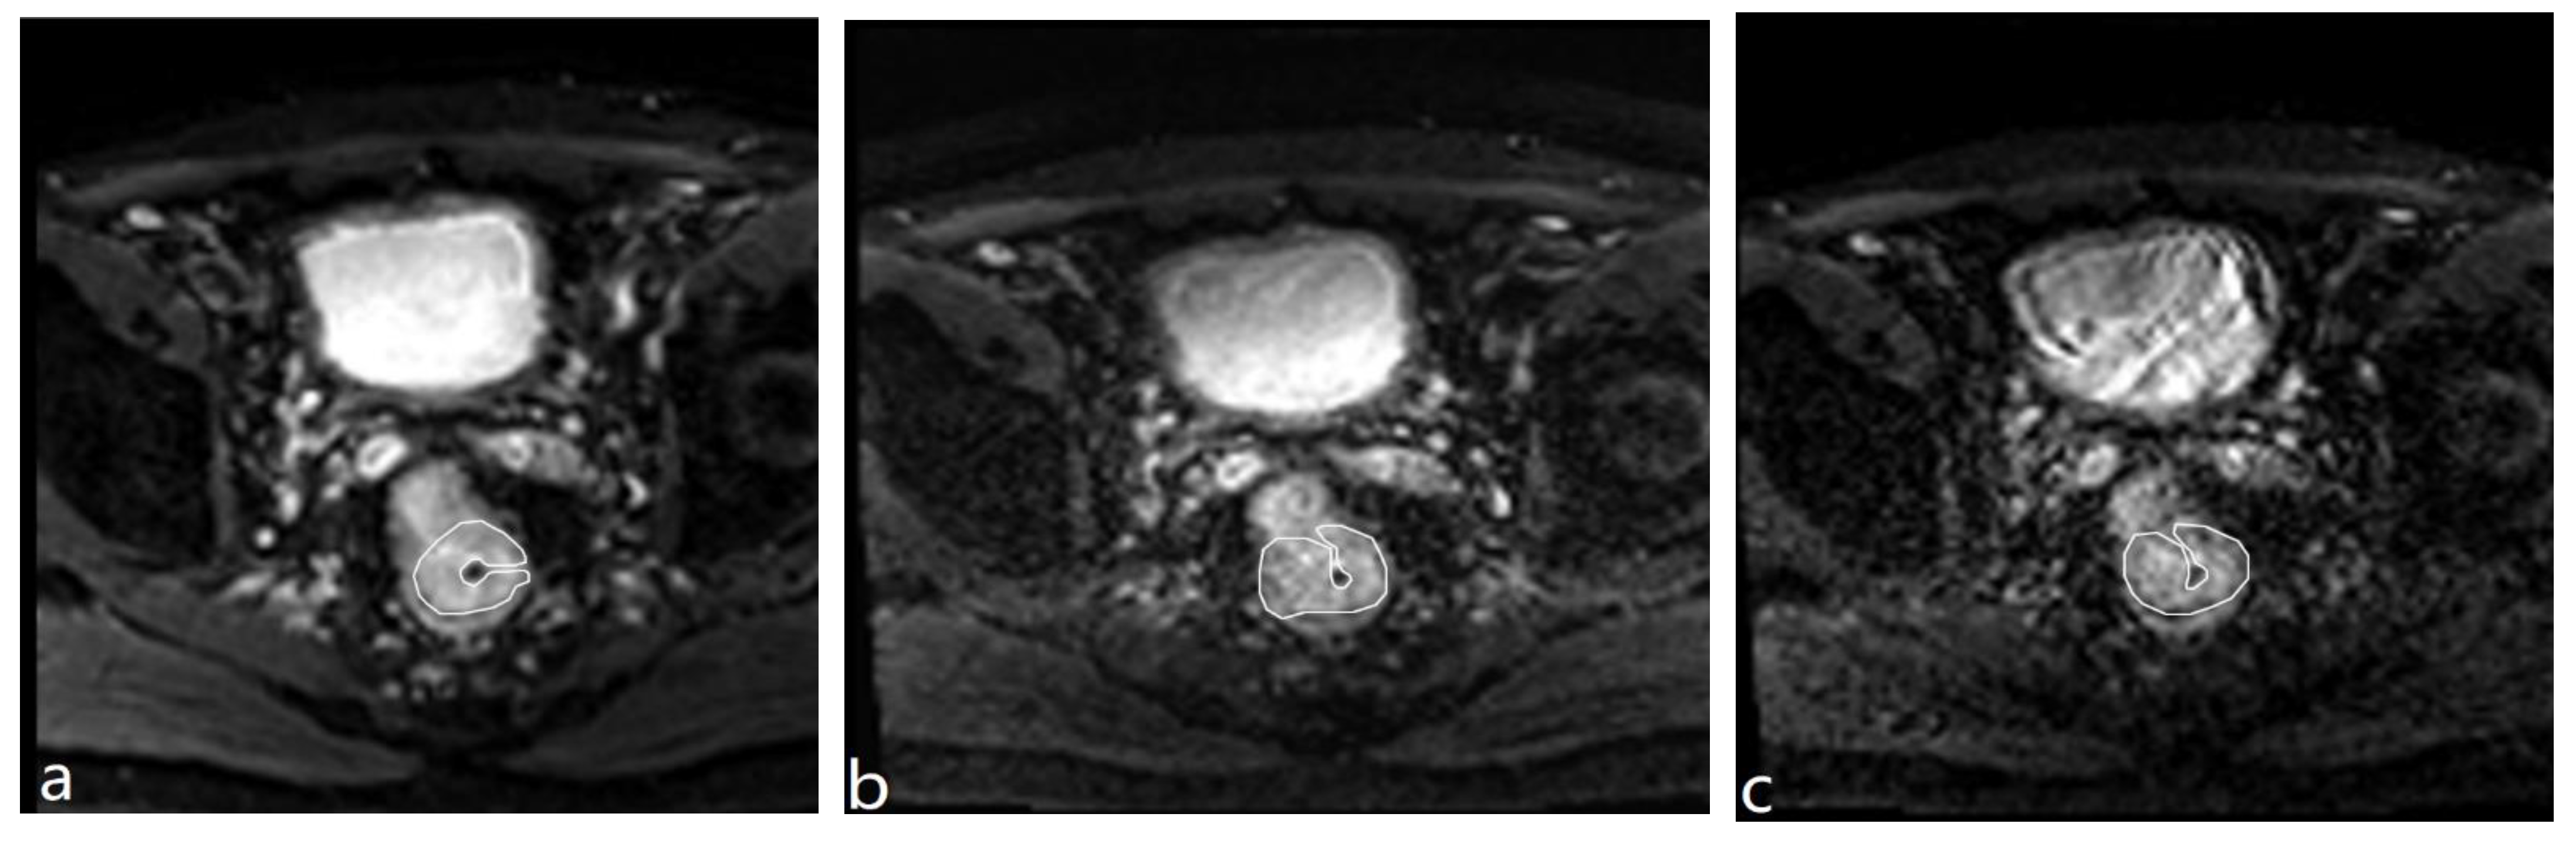

2.4. Image Quality-Quantitative Analysis

For quantitative analysis, the two radiologists performed the region of interest (ROI) measurement in consensus. First, two ROIs were drawn on the DWI images with b = 0 s/mm2 to include the largest possible areas of rectal cancer and normal rectal wall of the three groups, respectively. Then, the ROIs were copied to the DWI images with b = 1000 s/mm2 for rs-EPI and SMS rs-EPI to obtain the mean signal intensity and standard deviation (Figure 1). Signal-to-noise ratio (SNR) and contrast-to-noise (CNR) were calculated according to the following equations [19]:

Figure 1.

The ROI drawing for cancer lesions on the b = 0 s/mm2 maps of rs-EPI (a); 2 × SMS rs-EPI (b), 3 × SMS rs-EPI (c).